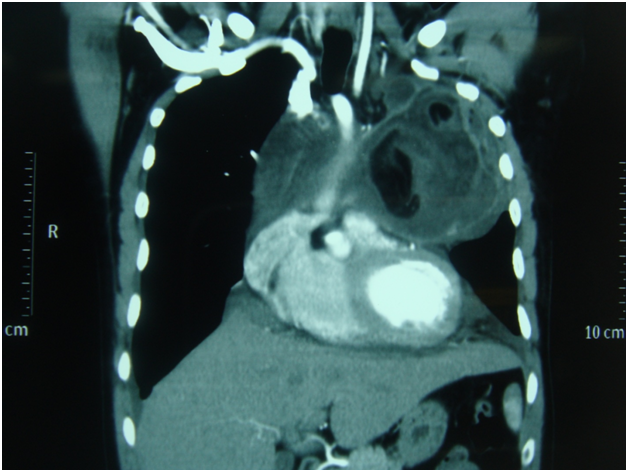

Figure 5 CT scan-- mature cystic teratoma -heart is pushed down.